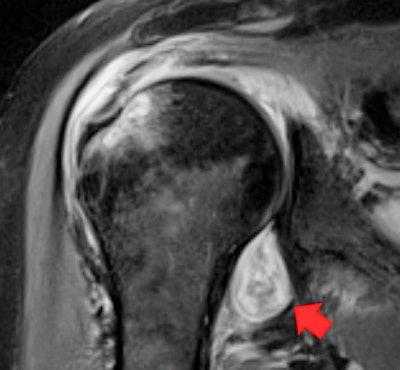

MRI image of a patient's shoulder. The red arrow points to inflammation in the joint. The COVID-19 virus triggered rheumatoid arthritis in this patient with prolonged shoulder pain after other COVID-19 symptoms resolved. Image courtesy of Northwestern University."We've realized that the COVID virus can trigger the body to attack itself in different ways, which may lead to rheumatological issues that require lifelong management," Deshmukh said in a statement released by the university. "Many patients with COVID-related musculoskeletal disorders recover, but for some individuals, their symptoms become serious, are deeply concerning to the patient or impact their quality of life, which leads them to seek medical attention and imaging."

"If a patient has persistent shoulder pain that started after contracting COVID, their primary care provider might order an MRI/ultrasound," he said. "If a radiologist knows COVID can trigger inflammatory arthritis and imaging shows joint inflammation, then they can send a patient to a rheumatologist for evaluation."